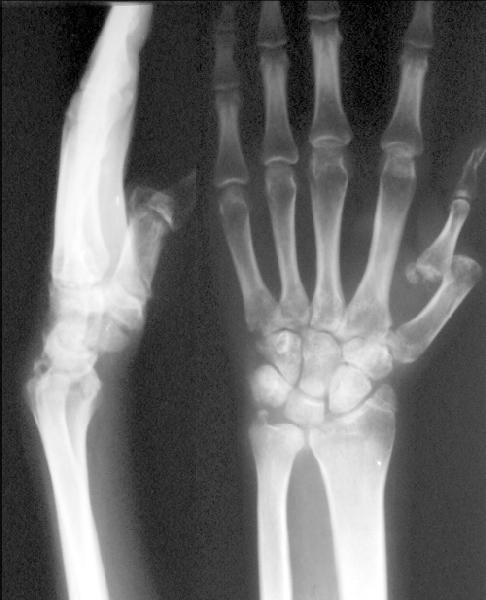

Сегодня поступил пациент, травма 2.04.02 при взрыве отопительного котла. Среди прочего на сегодня имеется нелеченный вывих I пальца левой кисти (см. приложение). Что оптимально сделать сейчас, спустя более 2 месяцев после травмы? Оставить как есть? Открыто вправить? Наложить дистракционный аппарат и постепенно вправить? С последующей разработкой в шарнирном аппарате? Заранее спасибо.-- Best regards, Alexander N. Chelnokov

This is a palmar dislocation. The main impediments to reduction would be the dorsal structures - EPB, EPL, APL. (Patel M, Dave J. Dislocations of the metacarpophalangeal joint of the thumb. Jr Hand Surg. (Br & Eur) 22-B; 4:

499-504) The sesamoids are seen close to the proximal phalanx, which suggests that the volar plate is intact apart from being pulled off the weak accordian attachment to the metacarpal head. I would suggest a lateral approach which would allow you to go both dorsal and palmar. Reduction, debridement of the arthrofibrosis and pinning (will give a stiff but stable MCP. One might be tempted to try dynamic ex-fix with early mobilisation to get some mobility.